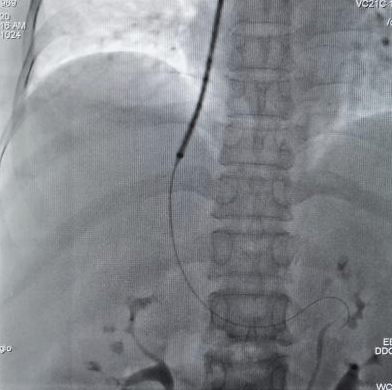

TIPS技术: